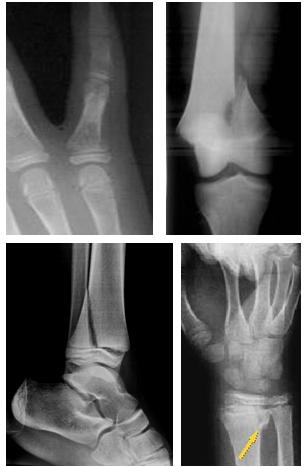

Si tratta di lesioni che si osservano nei bambini prima della saldatura della cartilagine di coniugazione e in cui la linea di separazione passa attraverso la cartilagine epifisaria per tutto il suo percorso o parte di esso. In questo secondo caso si associa una frattura dell’epifisi cartilaginea o di un nucleo epifisario oppure della metafisi.

I distacchi epifisari vengono classificati in puri e misti a seconda che vi sia coinvolgimento anche della metafisi o del nucleo epifisario. La classificazione più utilizzata nella pratica clinica quotidiana è quella di Salter-Harris che suddivide i distacchi in 5 tipi.

- Tipo 1: puro completo – in genere la consolidazione è rapida e non vi sono disturbi di accrescimento

- Tipo 2: più frequente in assoluto – oltre alla fisi è interessata obliquamente la metafisi – in genere la prognosi è buona

- Tipo 3: raro - interessa longitudinalmente la cartilagine di accrescimento e obliquamente l’epifisi – prognosi discreta

- Tipo 4: Interessata longitudinalmente la cartilagine di accrescimento e la metafisi coinvolgendo il nucleo epifisario ed interrompendo il periostio- prognosi più incerta

- Tipo 5: schiacciamento dello strato basale della cartilagine di accrescimento con scarso spostamento (spesso diagnosi difficile ed errata) - Prognosi cattiva.

Talvolta una precisa classificazione radiografica (specie in caso di scarso spostamento o in distacchi complessi) è complessa e si rende necessario un approfondimento diagnostico con RM.